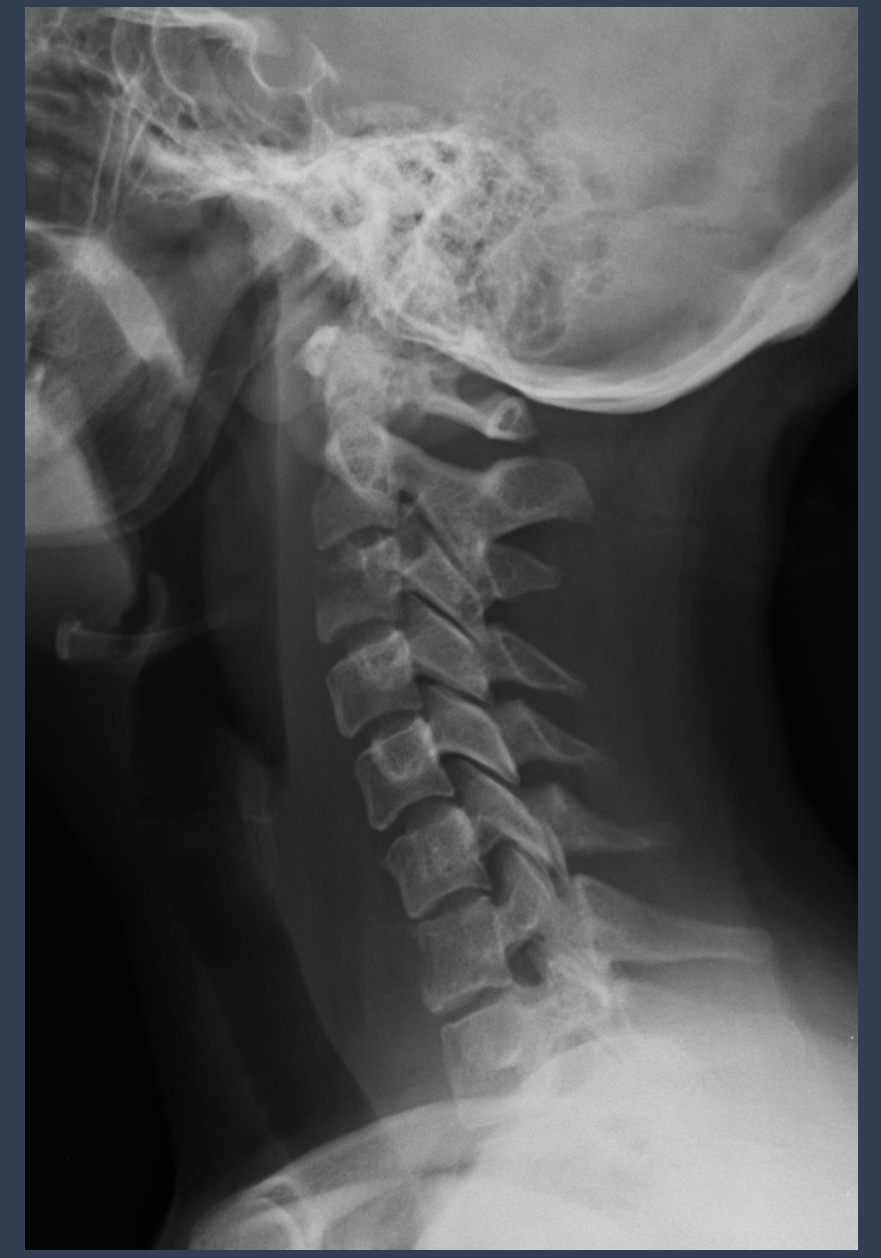

what condition is this?

describe it

tubercular spondylitis, Pott’s disease

decreased disc space. loss of cervical curve. ??